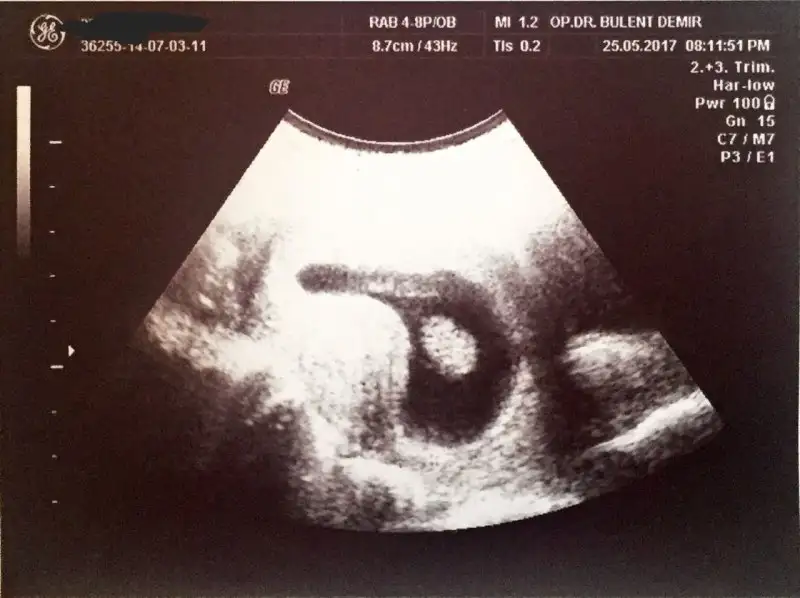

ayy allah razi olsun ya cevap verdgn icin cok sagol bi kac yere yazdm kimse yazmadi dogru düzgün.miyom falan yoktu en son bende ama dedgn gibi karin buyudugu icinde insallah yaa vallah 11 de yataga girip anca 3 te uyuyrm done done korkuyrmda bisey olcak diye.insallah dedgn gibidir ptesi gidicem yine zaten tedbir amacli dusuk onleyici ilaclarda iciyrm onlarda bitti sayilir.sagol tekrar allah saglikla kucagina almayi nasip etsin insallahCanım aynı haftalarda benimde başladı hatta gecenlerde burda yazmıştım hiç uyku uyuyamıyorum artık ama doktora sordum normal dedi hem karnımız büyüyor hem de benim miyomlarım var onlar agrı yapıyor